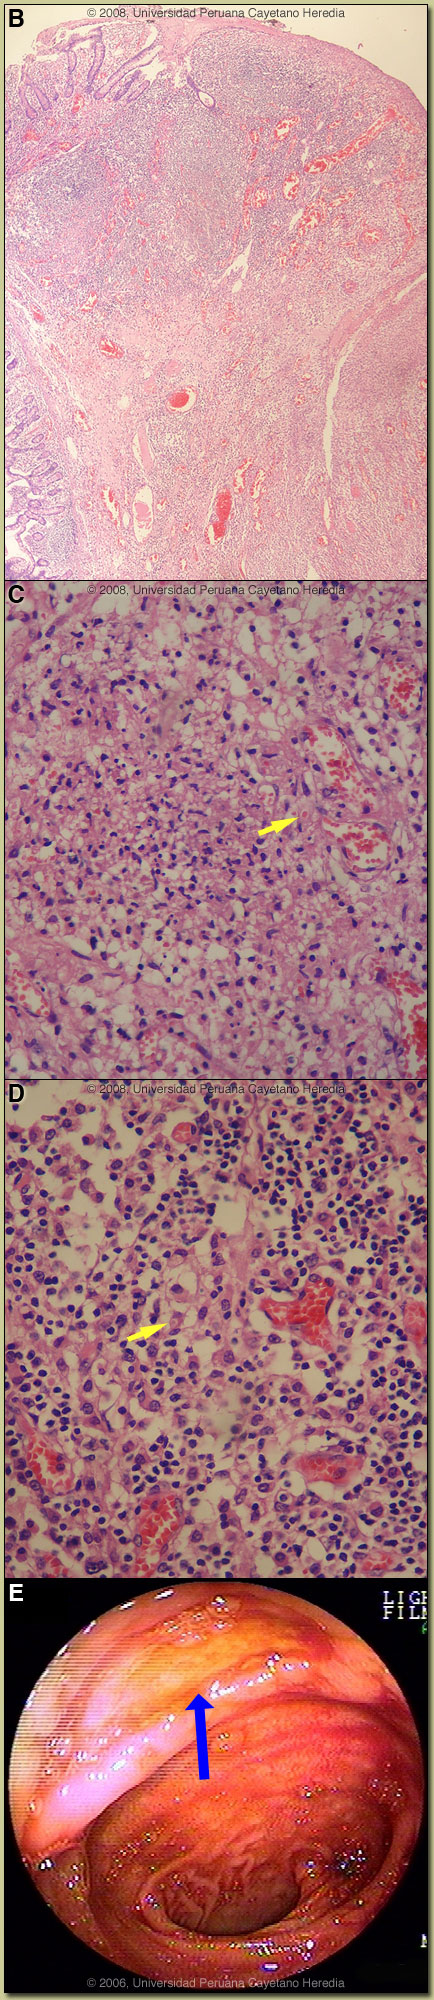

Discussion: The free air noted under the right hemi-diaphragm led to urgent laparotomy. A single perforation (0.5 cm) located 50 cm from the ileo-cecal valve was observed, multiple mesenteric enlarged lymph nodes were also seen, and approximately 200cc of clear fluid was present in the peritoneal cavity. A resection was performed with terminal anastomoses. A Widal test was positive with O 1/320, H 1/320. Image B shows the intestinal perforation surrounded by chronic inflammatory reaction. Image C shows a granulomatous reaction with epithelioid cells. The predominant infiltrate consists of aggregates of histiocytic cells, and is accompanied by some lymphocytes and plasma cells. “Typhoid cells” can also be seen with ingested red blood cells inside [arrow]. In Image D, the typical histopathological finding of so-called “typhoid cells”, tissue infiltration by aggregates of histiocytes containing bacteria and degenerating lymphocytes is shown [arrow].

Typhoid fever is a systemic febrile illness caused by Salmonella enterica sub-species enterica serotype Typhi. Prolonged fever, sustained bacteremia, and intracellular multiplication of the bacteria within mononuclear phagocytic cells of the liver, spleen, lymph nodes, and Peyer’s patches are hallmarks of the infection. Paratyphoid fever is a pathologically similar but milder disease caused by a number of other serotypes of Salmonella. Transmission is usually via contaminated food and water. S. typhi can survive for weeks in water, ice, sewage and on inanimate objects. Stool from chronic carriers can contain from 106 to 109 organisms. Ingested bacteria invade small intestinal epithelial cells and are initially internalized in intestinal lymphoid cells and draining mesenteric lymph nodes. At the end of an incubation period, which is generally 7-14 days but can vary from 3-60 days, clinical disease heralds the onset of the bacteremic phase of the infection. Bacteria may invade any organ but most commonly invade mononuclear cells within liver, spleen, bone marrow, gallbladder and Peyer’s patches. Involved Peyer’s patches are generally in the terminal ileum within 60 cm of the ileo-cecal junction and in the cecum itself. Without treatment, after about 7-10 days of illness, necrosis and sloughing of the overlying mucosa may result with ulcer formation [see Image E from another patient] and more rarely intestinal perforation. Ulcers are usually 1 cm or less in size and most often solitary. Most patients are children and young adults under 25. Clinical manifestations are protean and non-specific but almost always include fever and headache. The headache often results in insomnia. Fever is initially low-grade but by the second week is high (39-40°C) and sustained. There may be intermittent confusion and many patients have an apathetic affect. Complications occur in 10-15% and are more frequent in patients who have been ill for 2 weeks or more. While a large number of complications have been described, clinically obvious gastrointestinal bleeding (10% of all patients), intestinal perforation (1-3% of hospitalized patients), and encephalopathy are the most common. GI bleeding is serious in 2% of all cases. Other, but less frequent infections associated with intestinal ulceration of adenopathy would be intestinal tuberculosis or Yersinia infection. Entameba histolytica and Balantidium coli infection cause ulcers and perforation but would only be found in the colon. Peripheral blood cultures are positive in 40-80% of patients only reaching higher yields if 15 ml of blood are cultured because of the low numbers of organisms in peripheral blood with 80% of those being intracellular. Culture of bone marrow increases the yield to >95% and may remain positive even in the face of several days of antibiotic therapy. Blood cultures yield decreases after the first week of illness. Stool cultures are positive in 30% of cases of acute typhoid fever. The Widal test remains controversial because of highly variable sensitivity, specificity and predictive values in different settings. However, the highly positive Widal test in this patient with this characteristic clinical syndrome strongly supports the diagnosis. Drug resistance in Latin America has not occurred to the same extent as in Asia and other areas of the world. Most of the typhoid in Peru remains sensitive to ampicillin, chloramphenicol, and trimethoprim/sulfa. Nevertheless, oral quinolones remain the treatment of choice for uncomplicated typhoid due to insignificant rates of relapse and chronic carriage as well as faster times to fever resolution of quinolones compared to the older drugs. Quinolone resistant S. typhi, which has become highly prevalent in Asia, has not emerged in Latin America, so that empiric quinolone therapy can be initiated without reservation in those who acquire infection in Latin America. In febrile patients, clinicians often characterize a non-response of fever after 48 hours as an antibiotic failure and switch drugs. In typhoid fever, response to quinolones most often does not occur until Day 4 or 5 and with chloramphenicol it is usually longer. Many sources continue to list Peru as a highly endemic country for typhoid fever based on data and experience from the 1980s. The cholera epidemic that began in 1991 in Peru and other Latin American countries resulted in the implementation in Peru of many public health and infrastructure changes that had a dramatic bystander effect on typhoid fever incidence rates [Infect Dis Clin North Am. 1994 Mar;8(1):183-205] that remain to this day. Prior to 1991, 50-100 cases of typhoid fever presented each year to our hospital. At present, we only see about 20 cases per year though numbers have begun to increase again in the past 2 years. The patient was treated with IV metronidazole and ceftriaxone to cover both Salmonella and other intestinal flora. The clinical evolution was satisfactory; she was discharged after 7 days of parenteral therapy to complete 14 days with oral metronidazole and ciprofloxacin. |